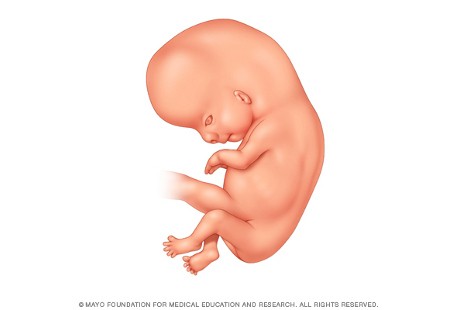

10. Minggu ke-11: Organ Genital Berkembang

Foto: AIUM.org

Di awal kehamilan 11 pekan atau 9 minggu setelah pembuahan, kepala janin yang masih terus disempurnakan bentuknya, memiliki ukuran sekitar setengah dari panjang keseluruhan. Untuk mengejar ketertinggalan, tubuhnya akan berkembang pesat dalam beberapa pekan mendatang. Nah, dengan bentuknya sekarang sudah bisa digambarkan sebagai janin.

Di pekan ini, dagu dan leher berkembang. Fitur wajah menjadi lebih jelas. Sementara itu telinganya bergerak lebih tinggi di kepala. Sel darah merah mulai terbentuk dalam hati janin. Pada akhir pekan ini, genitalia eksterna janin Anda akan mulai berkembang menjadi penis atau klitoris dan labia mayora.

Sel darah merah mulai terbentuk dalam hati janin. Pada akhir pekan ini, genitalia eksterna janin Anda akan mulai berkembang menjadi penis atau klitoris dan labia mayora. Sekarang panjang janin Anda dari puncak kepala sampai bokong sekitar 50 milimeter. Sementara itu beratnya hampir 8 gram.